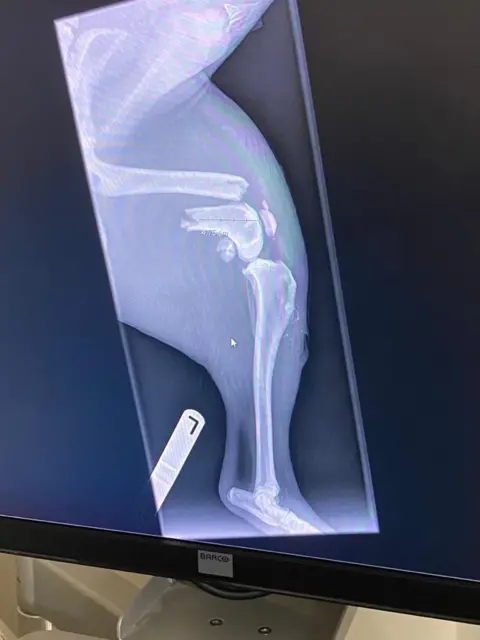

Oban suffered a broken leg and puncture wounds but managed to survive the steep drop.

Oban is expected to spend 12 months in recovery after surgery on his leg.